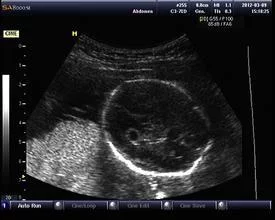

于孕龄在14~24周胎儿发育中超声检查发现的侧来自脑室脉络丛散在的、直径≥3mm的小囊肿。90%以上胎儿脉络丛囊肿在妊娠26360百科周以后消失,仅少数呈进行性增大。如果26周后还不消退,婴儿出生后可能会出现压迫和颅压增高等情况。

1.脉络丛强回声内见囊性暗区,囊壁薄边缘光滑,整齐,多呈圆形客周括。囊肿可单发,也可多发。